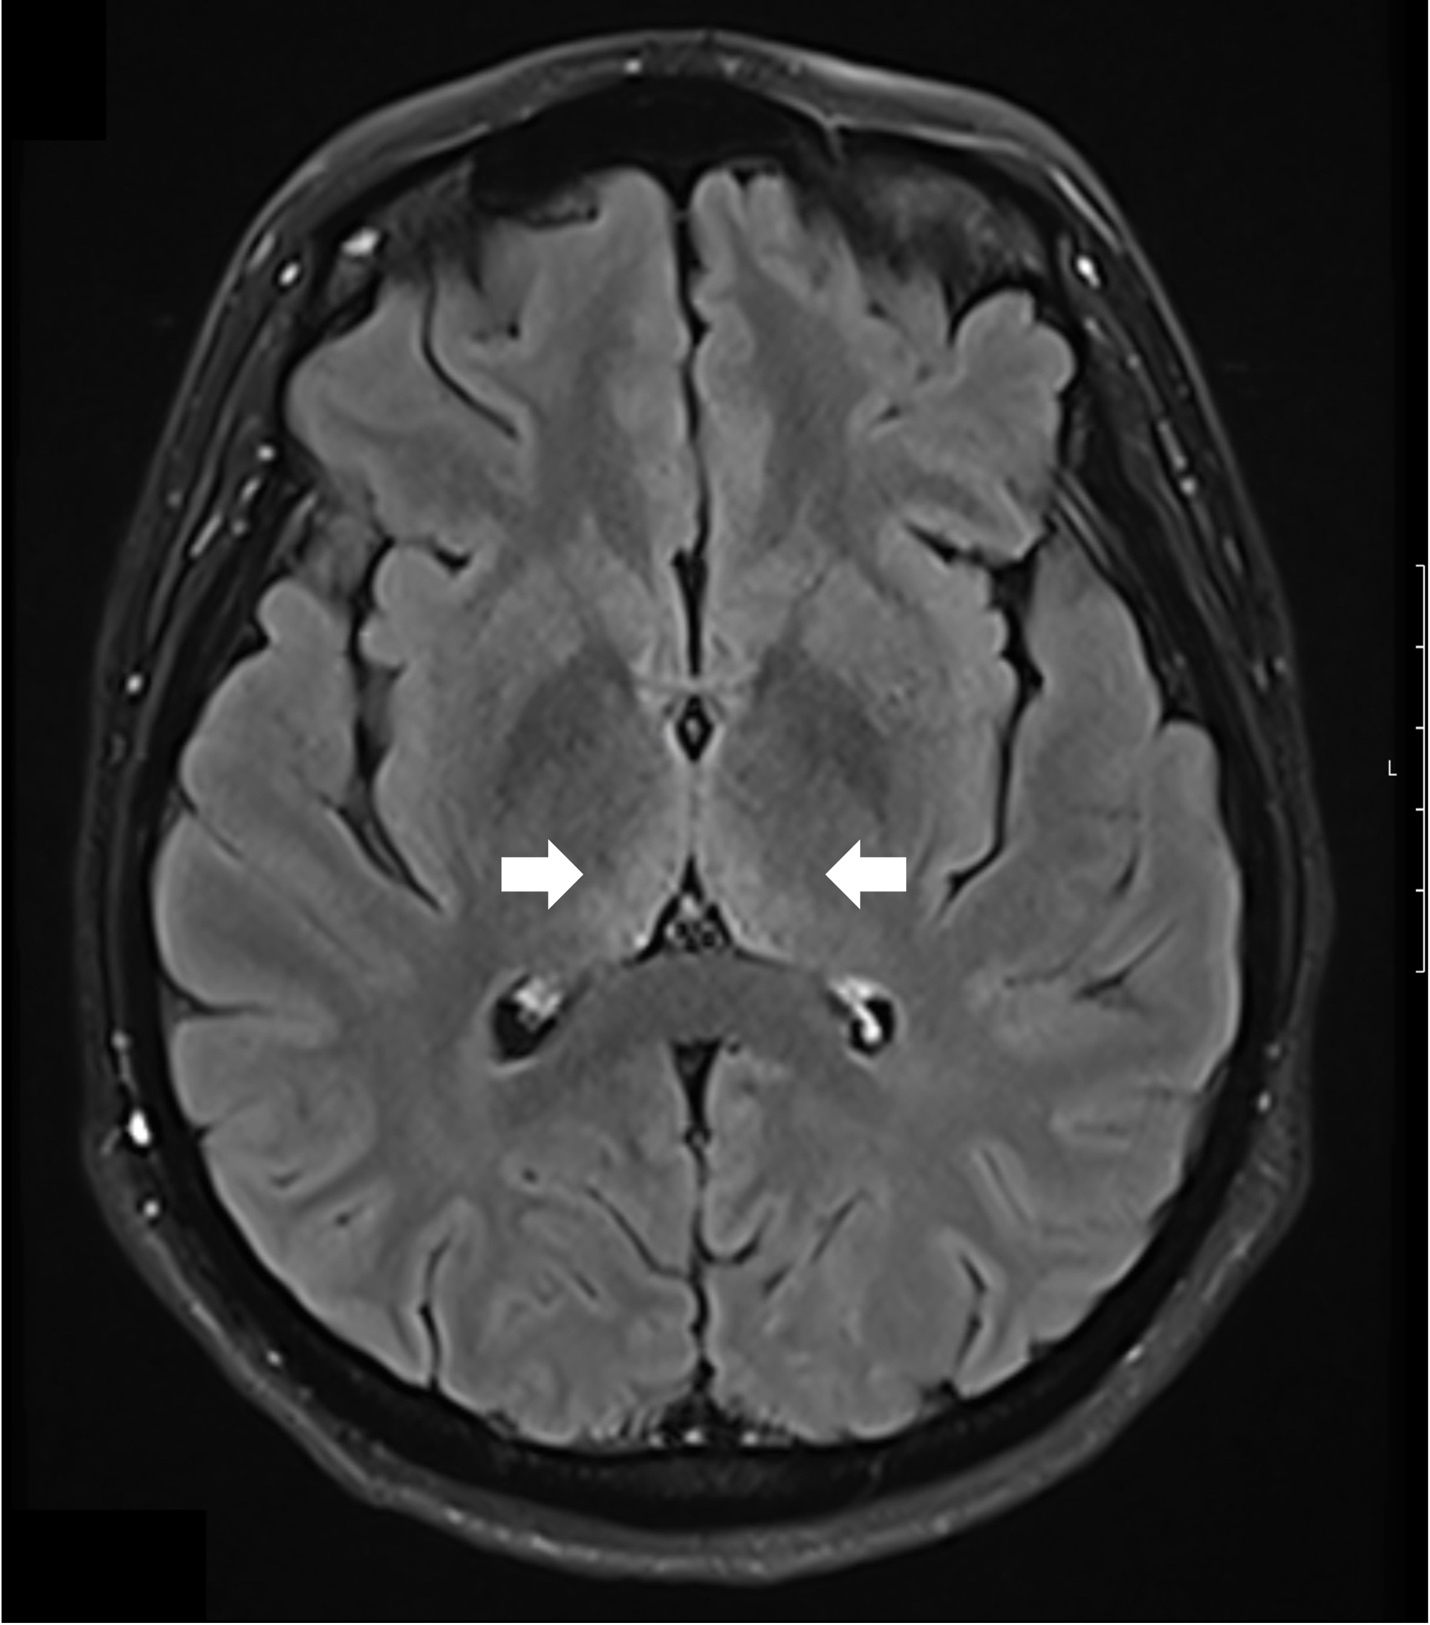

The patient was started on high-dose intravenous thiamine therapy, following established guidelines for the management of Wernicke’s encephalopathy. Based on recommendations from the European Federation of Neurological Societies (EFNS), she received 500 mg of intravenous thiamine every 8 hours for 3 days to rapidly replenish thiamine stores and prevent further neurological deterioration. This was followed by a maintenance dose to support continued recovery and prevent relapse. As her symptoms improved, particularly nausea and abdominal discomfort, she was able to tolerate oral intake. Her diet was gradually advanced to a standard oral regimen as clinical stability was achieved. Repeat MRI brain showed resolution of thalamic hyperintensities at 3 months follow-up (Figure 2)